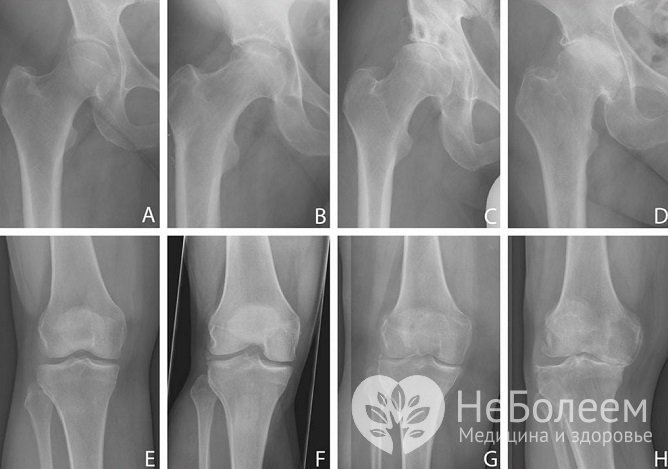

Рентгенологическая диагностика является наиболее информативной и не требует больших финансовых затрат.

Наиболее информативным методом диагностики заболевания является рентгенВ настоящее время используется рентгенологическая классификация остеоартроза, включающая 4 стадии развития процесса:

Остеофиты – костные разрастания – являются ранним рентгенологическим признаком заболевания. Они появляются одними из первых и свидетельствуют об активной пролиферации структур соединения. По мере прогрессирования они утолщаются, превращаясь в массивные костные шипы.

Сужение суставной щели является признаком патологических процессов в хряще. Иногда щель приобретает клиновидную форму, при которой одна половина суживается, а другая расширяется. Это косвенно указывает на нестабильность сочленения и недостаточность связочного аппарата.

Появление признаков остеосклероза свидетельствует о прогрессивной потере хрящом амортизирующей функции, атрофии, что ведет к уплощению и расширению головок суставных поверхностей, увеличению плотности кости. Результатом поражения хряща является возникновение очаговых дистрофических, некротических процессов в губчатой кости и, как следствие, появление кистовидных образований.